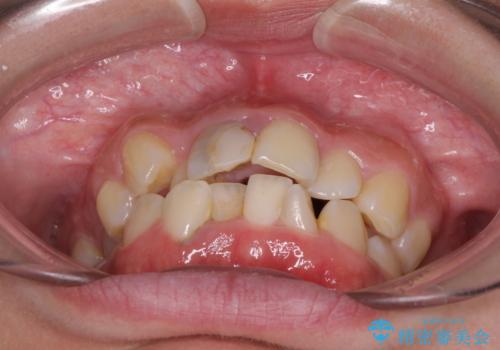

虫歯と抜いたままの奥歯とデコボコの前歯 総合歯科治療

- 放置した虫歯や抜いたままの奥歯、前歯のデコボコを気にして来院された患者様です。

口元の突出感は少なく、下顎の叢生は軽微なものであったので、叢生の強い上顎左右の小臼歯を1本ずつ抜歯し、ワイヤー装置にて矯正治療を行うこととしました。

矯正治療をしたいと思っていたが、放置している虫歯が多いため、どこに相談に行けば良いのか分からずにいたそうですが、当院の総合歯科診療を見て来院されたそうです。